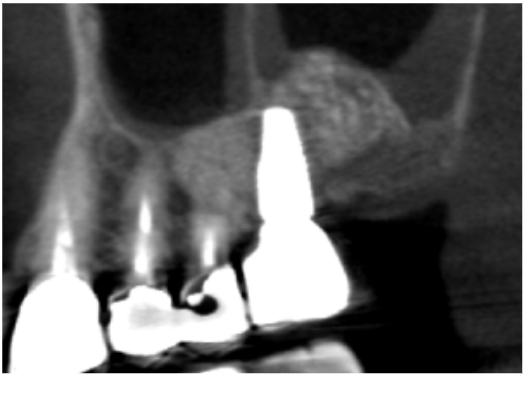

症例1

| 項目 | 詳細 |

|---|---|

| 患者様データ | 60代 女性 |

| 来院時の主訴 | 「インプラント治療を受けたい。」 |

| 医院の診断 | 歯牙欠損、重度の顎堤欠損、角化歯肉不足 |

| 通院期間 |

6か月 |

| 来院回数 | 4回 |

| 治療費 | 総額:250,000円(税抜) 【内訳】 GBR(骨再生手術)250,000円 |

| リスクと副作用 | 術後の腫れと痛み |

| ここがこだわりのポイント!☝ | 歯周病により失ってしまった骨を再生することができました。 |